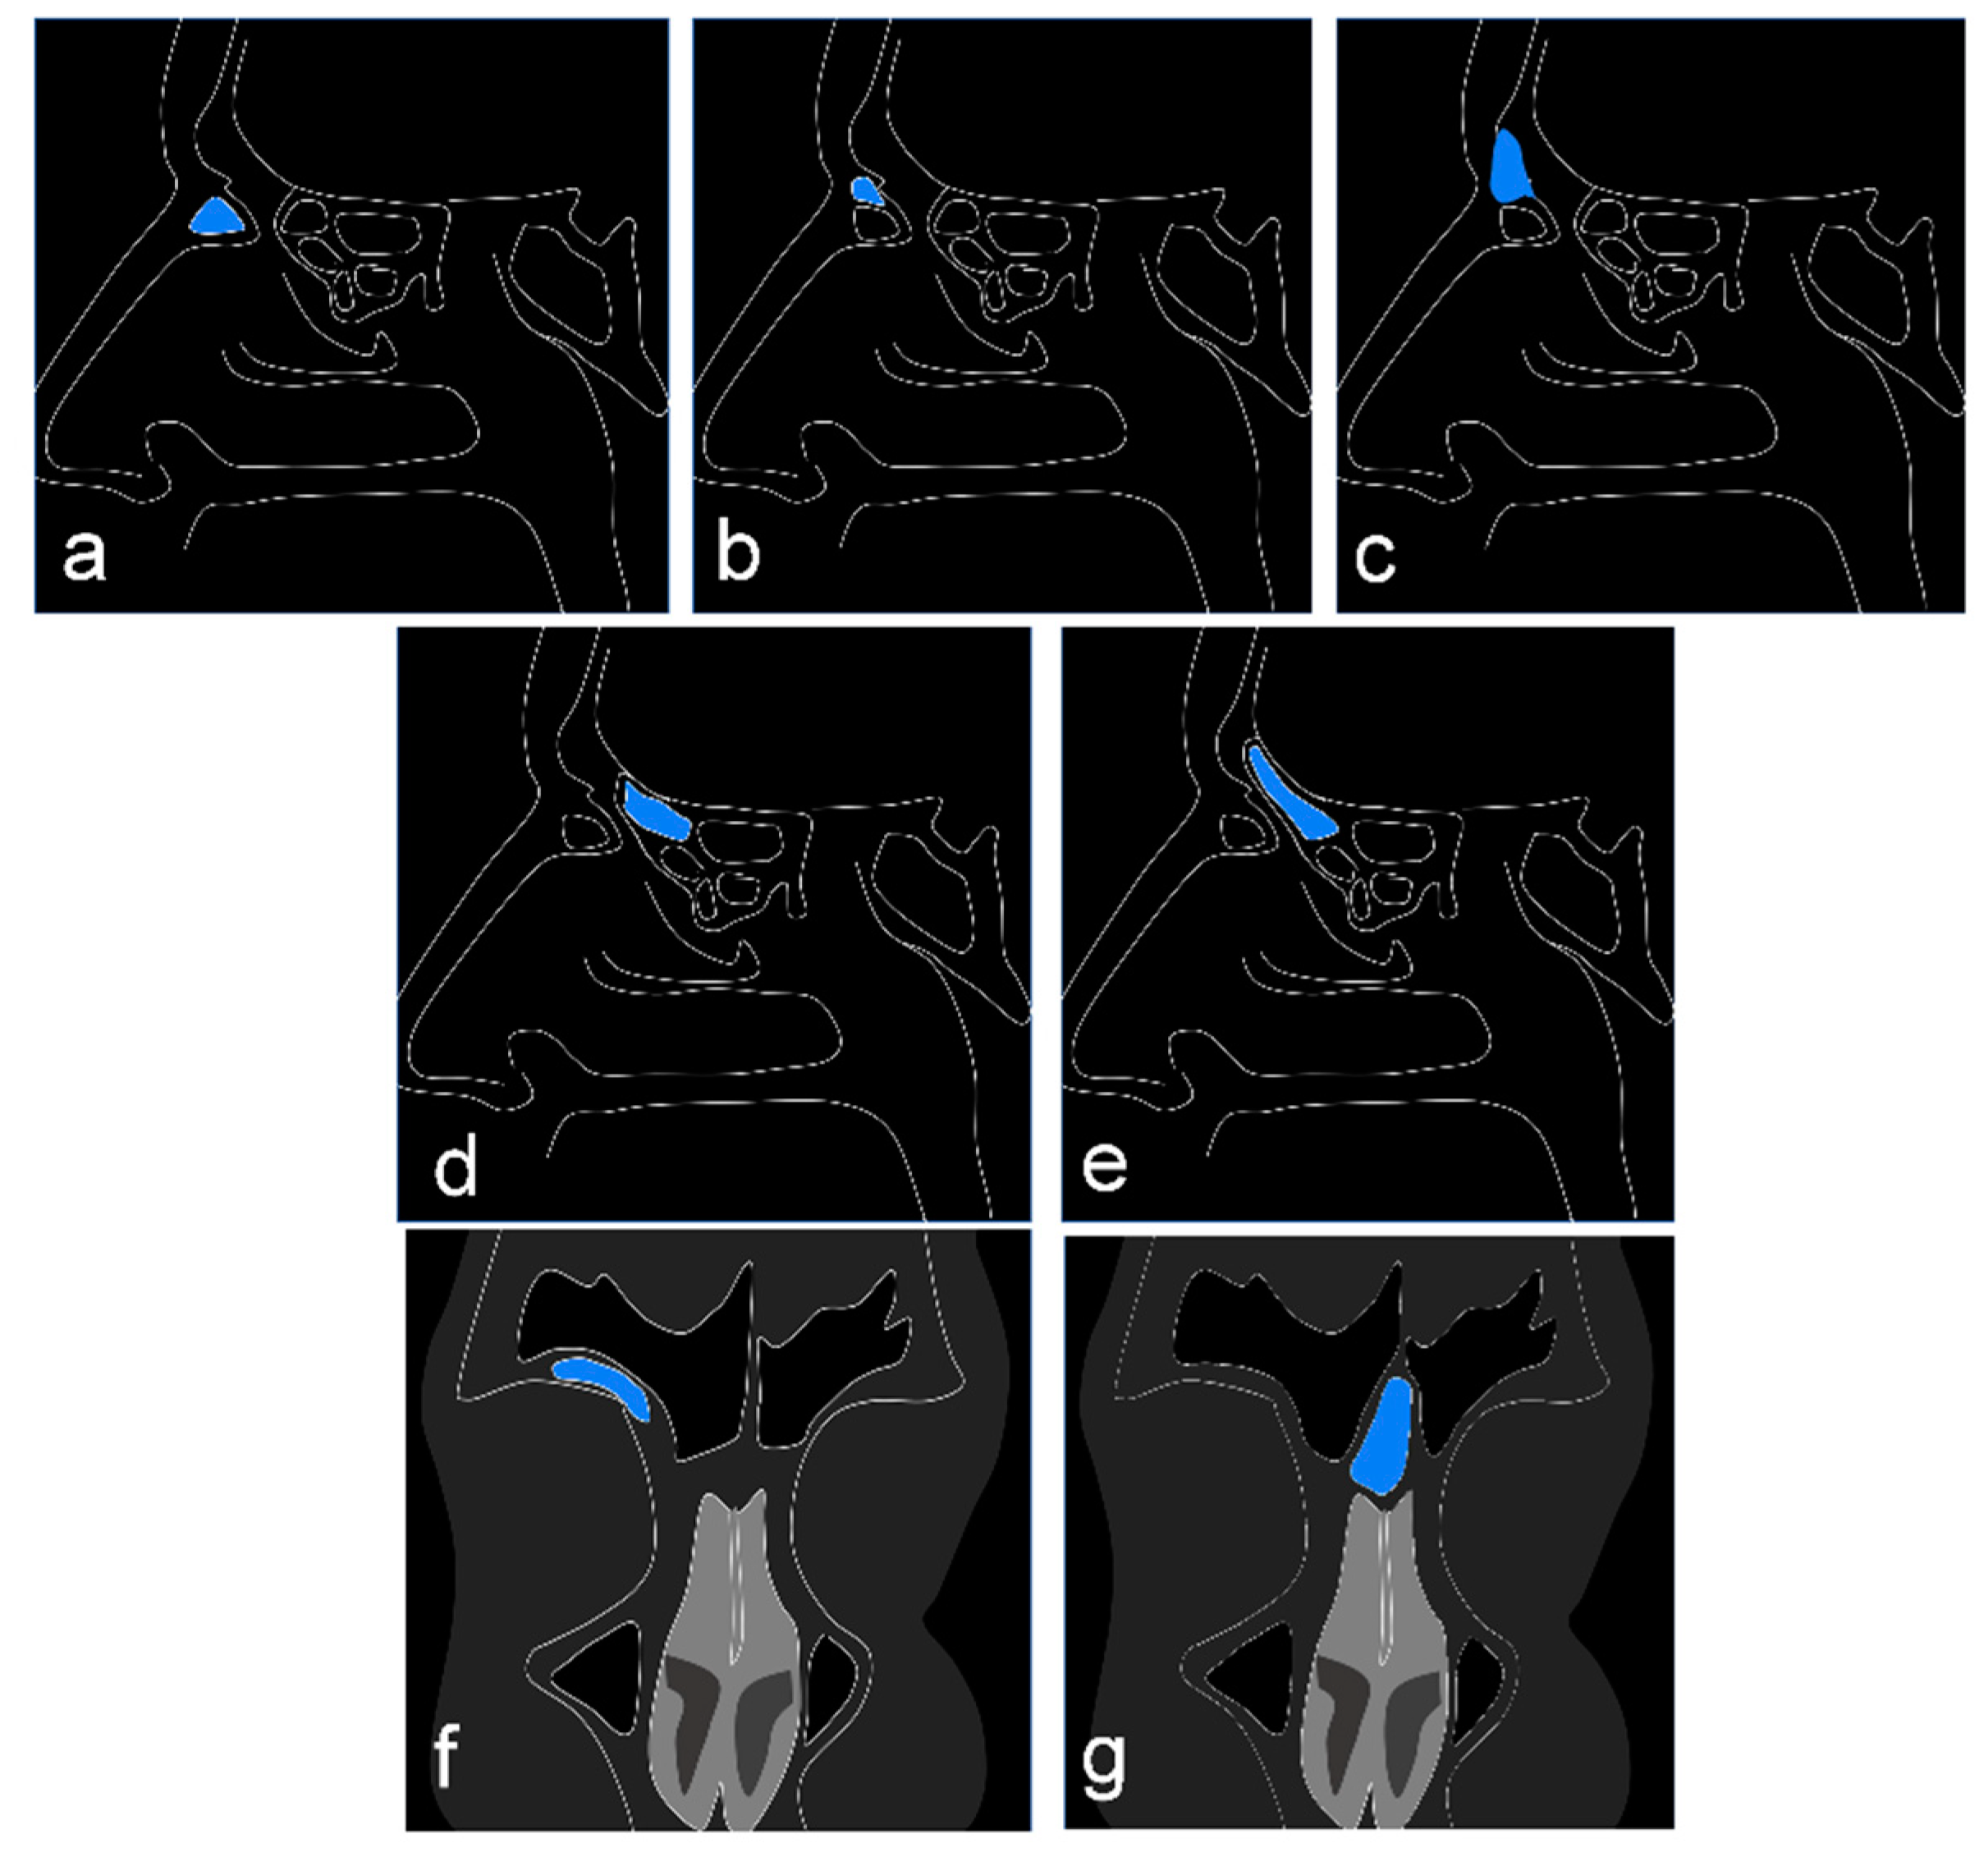

2.2. Identification and Data Extraction

3.1. Agger Nasi Cell

3.2. Supra Agger Cell

3.3. Frontal Septal Cell